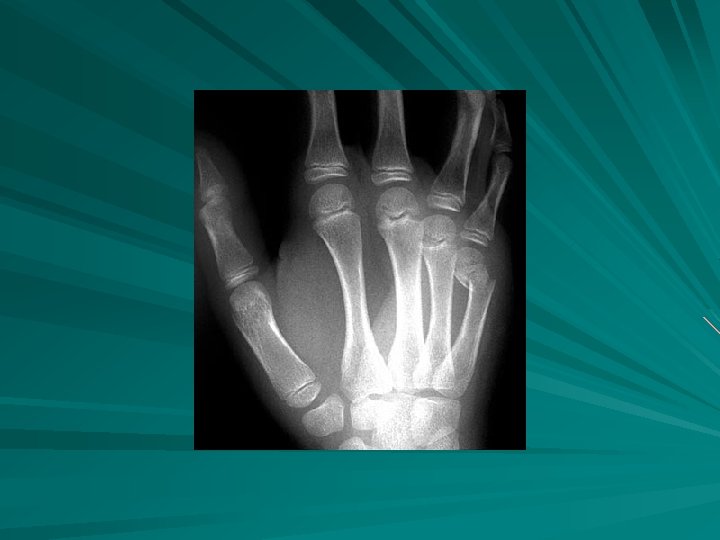

FX RADIAL HEAD